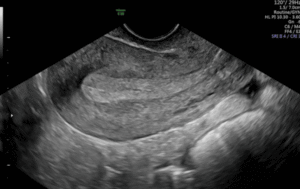

Siêu âm phụ khoa qua ngã Âm đạo

Siêu âm kiểm tra tử cung + buồng trứng Mục đích: kiểm tra phát hiện bất thường như nhân xơ tử cung, u nang buồng trứng, đánh giá nội mạc tử cung, phát hiện thai sớm,….

Siêu âm khảo sát dị tật thai (20-24 tuần)

Siêu âm khảo sát hình thái 3 tháng giữa cho thai nhi nhằm phát hiện các bất thường về cấu trúc

Siêu âm doppler thai kết hợp chụp ảnh bé 4D

Siêu âm thai, đánh giá sự phát triển của thai, ước lượng cân nặng, đánh giá sức khoẻ thai, kiểm tra lượng nước ối, trở kháng động mạch rốn, động mạch não giữa,…

Siêu âm đo độ mờ da gáy + Khảo sát hình thái quý 1

Sàng học các bất thường hình thái học và các việc tiếp cận theo protocol một cách có hệ thống đang ngày càng tăng độ nhạy phát hiện dị tật nhiều ở dân số nguy cơ thấp ở ngay trong lần siêu âm đầu tiên.